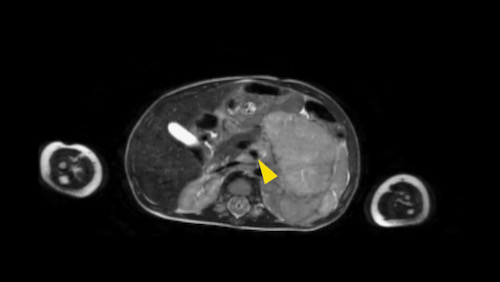

Hình ảnh MRI của một bé gái chín tháng tuổi có khối u ở bụng trái. MRI cho thấy khối u tuyến thượng thận trái, một phần đặc, một phần nang. Có nhiều di căn gan.

Khối u đã được sinh thiết. Có tình trạng chảy máu liên tục qua kim dẫn đường. Vào cuối thủ thuật, hai nút bọt gelatin đã được đặt vào (các dải tăng âm (mũi tên)).